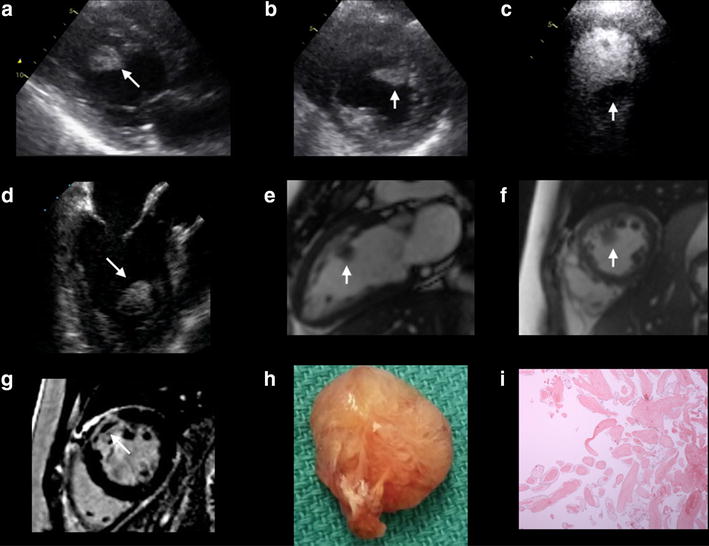

A 43-year-old Caucasian woman with type II diabetes, hypertension, dyslipidemia, and pre-existing ischemic heart disease (IHD), presented with a non ST-segment elevation myocardial infarction (NSTEMI). Coronary angiography demonstrated multi-vessel disease with severe in-stent restenosis of her proximal left anterior descending (LAD) and significant obstructive lesions in the proximal right coronary artery (RCA) and proximal obtuse marginal (OM) artery. Given the multi-vessel disease with two layers of stent and aggressive nature of her coronary artery disease, the patient was accepted for in-hospital coronary artery bypass grafting (CABG). A preoperative transthoracic echocardiogram (TTE) confirmed a mass (23 × 18 mm) within the LV cavity (Fig. 1a, b). Following the administration of Definity for LV opacification, the mass appeared avascular, mobile, with a broad based attachment to the mid anterior wall (Fig. 1c). Transesophageal echocardiogram confirmed the size and attachment of the LV mass to the anterior wall (Fig. 1d). Cardiac magnetic resonance imaging confirmed a LV mass measuring 1.3 cm adjacent to the akinetic mid-anterior wall (Fig. 1e, f). Following the administration of gadolinium, delayed enhancement imaging confirmed infarction of the mid to basal anterior wall without enhancement of the LV mass (Fig. 1g). As there was no evidence of late gadolinium enhancement of the LV mass on CMR, this would favor a presumed diagnosis of a LV thrombus. The patient underwent surgical resection of the mass via the aortic valve during a four vessel CABG procedure, including left internal mammary artery to LAD, left radial artery to posterior descending artery, saphenous venous graft to first obtuse marginal artery, and a second saphenous venous graft to the second obtuse marginal artery. The gross specimen of the LV mass demonstrated a 22 × 16 × 10 mm mass with a characteristic frond-like appearance, suggestive of papillary fibroelastoma (Fig. 1h). Histopathological examination confirmed an avascular connective tissue core with adjacent fronds covered by endothelium consistent with a papillary fibroelastoma (Fig. 1i).

Fig. 1.

a, b A parasternal long axis and short axis view on TTE demonstrating an echodense mass (23 × 18 mm) attached to the mid anteroseptal wall of the LV; c An apical 4 chamber view on TTE following the administration of Definity demonstrating the avascular nature of the mass within the LV cavity; d A midesophageal long axis view on TEE confirming the echodense mass attached to the mid anteroseptal wall; e, f A vertical long axis and short axis view on B-SSFP imaging using CMR demonstrating the location of the intracardiac mass within the LV cavity; g A short axis view on DE-CMR confirming infarction of the mid to basal anterior wall; h Gross specimen of the LV mass (22 × 16 × 10 mm); i Histopathological confirmation of an avascular connective tissue with fronds covered by endothelium consistent with a papillary fibroelastoma